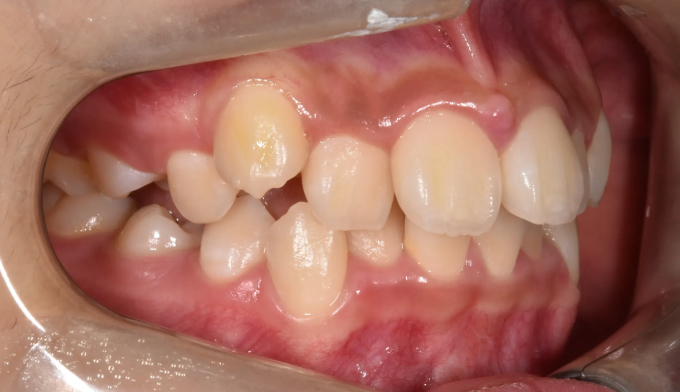

위턱, 아래턱 모두 치아 배열 공간이 부족한 경우 입니다.

확장장치를 이용해 공간 부족을 해결하고 치열을 배열하면 간단히 끝낼 수 있습니다.

이때 입술의 두께나 위치, 위아래 앞니의 각도를 종합적으로 고려하여야 합니다.

치아를 배열한다고 앞니가 뻐드러지면 잘못된 교정치료입니다.

총 치료기간은 20개월 소요되었습니다.